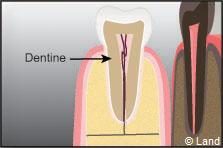

La dentine est composée d’une trame moins minéralisée, située sous l’émail.

Dans la partie centrale de la couronne se trouve la pulpe innervée et vascularisée. L’intérieur de la pulpe est rempli de vaisseaux sanguins et de nerfs. Ces nerfs donnent la capacité de réagir au chaud, au froid et à la douleur. Les vaisseaux sanguins procurent l’alimentation à la dentine, permettant la réparation de cette dernière lorsque la dent subit un traumatisme.